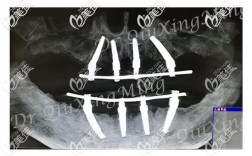

- 影像学检查:需拍摄CBCT(锥形束CT),三维观察牙槽骨量、神经管位置、上颌窦底情况,确保种植体植入路径安全;若怀疑牙根残留或根尖病变,还需配合根尖片。

- 备洞与植入种植体:根据CBCT数据,用专用钻针逐级备洞(直径从2mm逐步扩大至与种植体匹配),将种植体(纯钛或钛合金材质)植入牙槽骨,理想位置为唇侧骨板1.5-2.0mm、根尖距下颌神经管≥2mm、距上颌窦底≥1mm。